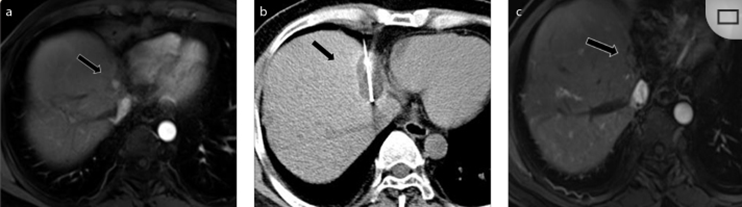

( a ) 軸向 MRI 和 ( b ) 軸向 CT 顯示肝S8段有一個16mm的病灶,鄰近肝緣。( c )冷凍消融期間CT顯示放置了2個冷凍探針,低密度冰球包圍病灶。(d)術后1個月隨訪 CT顯示冰球對應的壞死區域,未見復發。(f)與基線影像(g)相比,12個月后的FDG-PET/CT顯示未見FDG攝取。

(a)軸向CT顯示病變位置毗鄰心臟和上腔靜脈(黑色箭頭)。1個月后的軸向(e)和冠狀位(f)增強CT掃描顯示低密度區域,由于肉芽組織反應引起的邊緣增強。